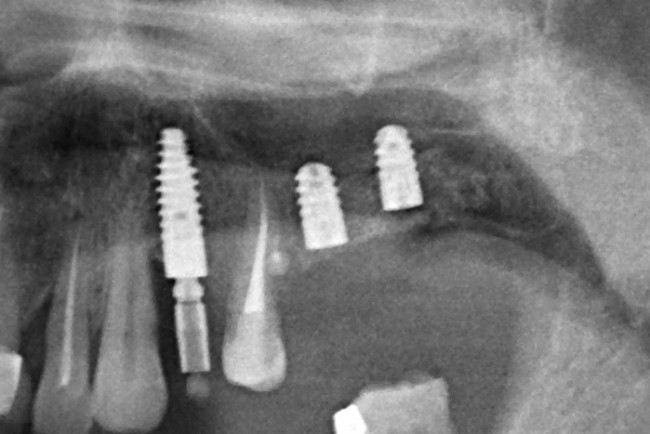

Имплантация и остеопластика: вместе или врозь? Часть II плюс Ankylos, плюс Geistlich